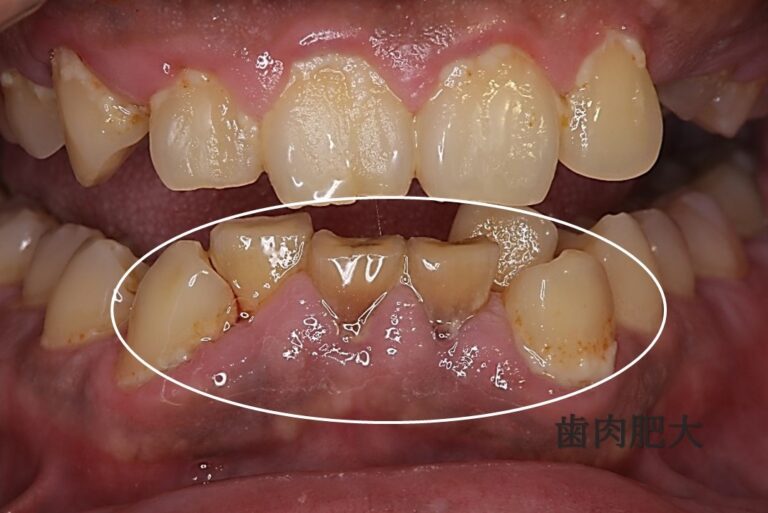

歯肉増殖症(しにくぞうしょくしょう)とは、歯周病の一種で、種々の原因によって歯肉の過形成が起こることである。

歯肉の組織の増殖と、血管の反応性の変化が合併したもの。浮腫は辺縁歯肉に限局している。歯肉溝から滲出液が確認されることもある。 口呼吸があると発症しやすい。